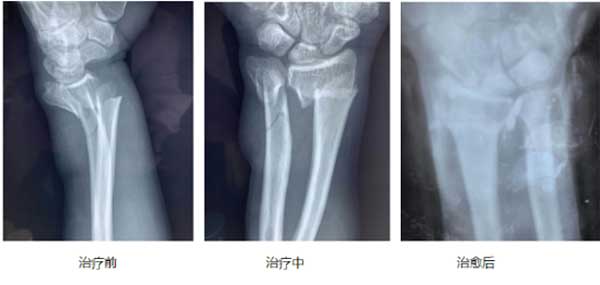

高大伟根据多年的推拿经验,将推拿的108种手法总结为“心到、意到、气到、神到、力到”五个标准。归纳出了正骨心法,即:安神宁心、调息自律,意随心动、气由血生,意气同到,力发可透,开皮通脉,弹筋错骨,一气呵成,尽在自然。创的高氏疗法,是经过高大伟医师20多年的不懈努力钻研,探索反复实践,及传统中医、药、针、刀、手法于一身、深入挖疗法”。针对的疾病例如股骨头、腰椎病、膝关节、颈椎病、肩周炎等。

高氏疗法的特点;在治疗的过程中不断总结经验,在治疗腰椎间盘突出合并椎管狭窄的临床经验中总结出了自己独特的经验。归纳起来就是“高氏三步四法”